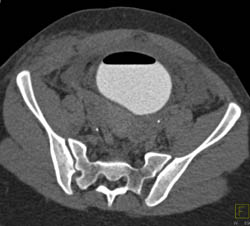

Bone Cyst Vs Fibrous Dysplasia